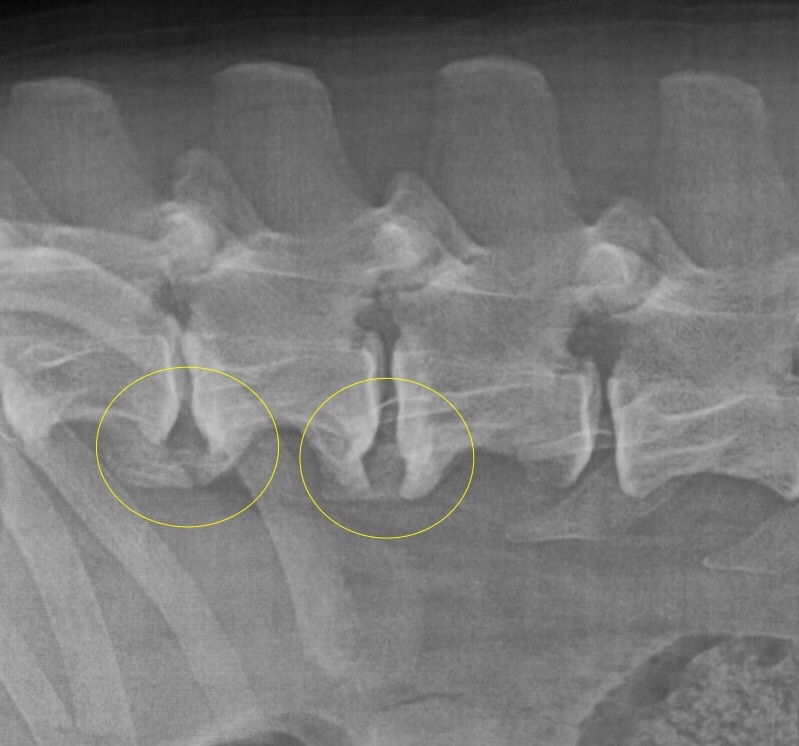

Nichts geht mehr? Urmels neue Menschen ergreifen den letzten Strohhalm. Ende April 2017 wird Urmel von ihrer Pflegerin Fatma nach Schweinfurt gefahren, um sie hier im Tiergesundheitszentrum näher zu untersuchen. Nach einer Gangbildanalyse (die bei einem so schwerfällig und nur mit Unterstützung einer Tragehilfe laufenden Hund natürlich nur eingeschränkt möglich ist) werden nach der anschließenden etwa zweistündigen orthopädischen Untersuchung aller Gelenke noch weitere Röntgenbilder von den Gelenken angefertigt, die in der Türkei nicht untersucht worden sind. Es zeigt sich, dass der Zustand noch schlechter ist als eh schon befürchtet: Urmel hat auch Arthrosen an der Wirbelsäule und weiteren Gelenken. Schließlich werden Urmel insgesamt 62 Berlock-Goldimplantate (das sind kleine spulenförmige Goldimplantate aus Dänemark) implantiert.

Infolge einer Gewichtsverlagerung bei solchen an einem Gelenk schwer gehandicapten Hunden kommt es über die Monate zu Folgeschäden an anderen Gelenken. Diese Schäden können sich bis zu den Zehengelenken ausdehnen. Häufig sehen wir dabei Arthrosen an den Zehengrundgelenken. Nicht selten sind die Sesambeine dieser Zehen frakturiert, durch Überlastung richtiggehend zerbröselt. Gerade solche Schäden aber werden leider zu oft übersehen. Wird eine solche Sesambeinfraktur übersehen, lahmt der Patient trotz aller weiteren Maßnahmen meist weiter. Da nutzt auch die beste Rekonstruktion der Patella am Knie nichts.